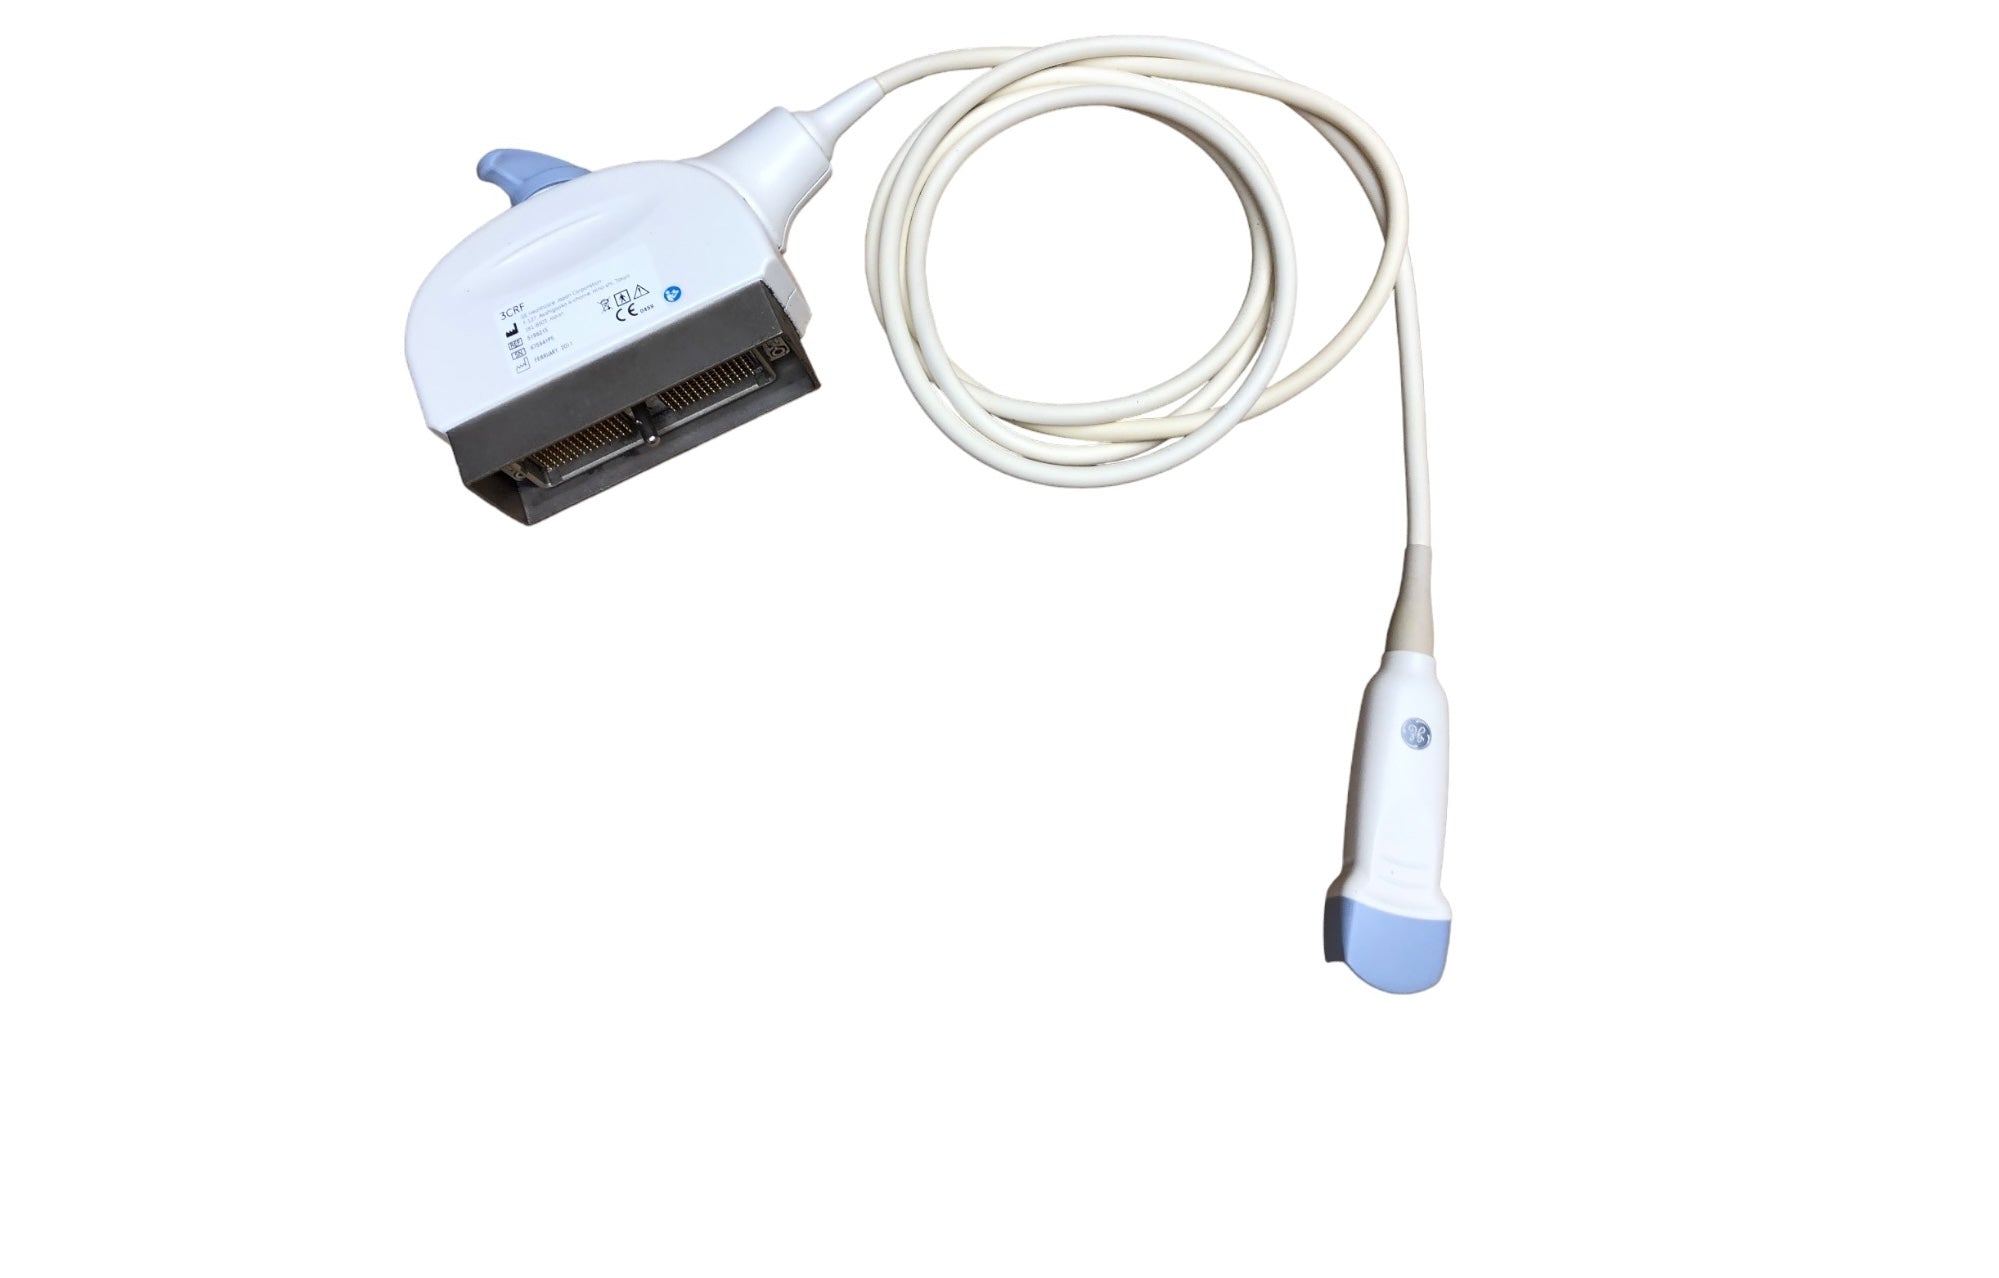

DIAGNOSTIC ULTRASOUND MACHINES FOR SALE

GE 3CRF Ultrasound Probe Transducer DOM 2011

Sale price$ 2,089.60